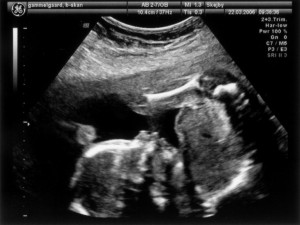

Vi har så endelig været på Skejby Sygehus, hvor specialisterne skulle vurdere babys hjerte. Konklussionen var at baby og hendes hjerte ikke fejler noget - alt er i den skønneste orden. Der blev foretaget en meget grundig skanning og billederne blev vurderet af en afdelingslæge, en overlæge samt en overlæge med mange års international erfaring i børns hjertefejl. Det var en stor lettelse at hun ikke fejler noget. Baby blev undersøgt generelt en gang til at specialisterne og alt er som det skal være. De kunne desuden konstatere, at det er en pige... Du kan se de billeder vi fik fra skanningen herunder.

Baby ligger med hovedet nederst i midten og kigger op. Hun flekser så meget i ryggen at hendes ben går helt op over hovedet. Babys hjerte med nogle målinger.